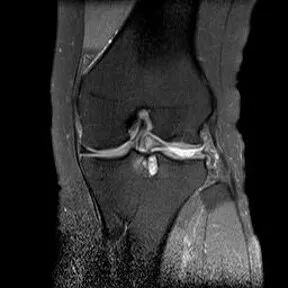

桶柄状撕裂MRI表现

1、宽度减小,在通过半月板体部的冠状面上蝶形消失,同时可见内移的半月板位于髁间窝、交叉韧带旁2、矢状面示残余的前角或后角变小或截断3、半月板前(后)角增宽或双半月板前(后)角征4、双前交叉韧带或双后交叉韧带征

半月板撕裂:桶柄状撕裂(双前角征)